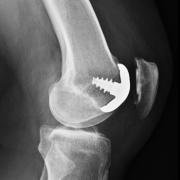

This is an X-ray showing a tibiofemoral partial knee replacement. The metal shows up as white, and the gap between the two metalllic bits is the plastic spacer (which does not show up on X-ray).